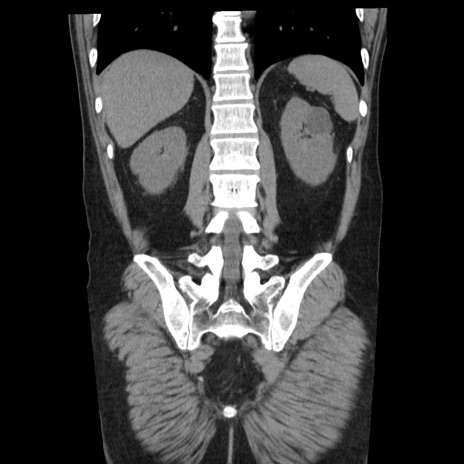

症例29(冠状断像)

【症例】40歳代男性

【現病歴】2日前から胃痛あり。徐々に周期的な激痛に変化した。本日になっても激痛があるため受診。

【身体所見】意識清明、BT 38-39℃台あり、腹部:膨満、やや硬、右下腹部に圧痛あり。

【データ】WBC 8500、CRP 23.26